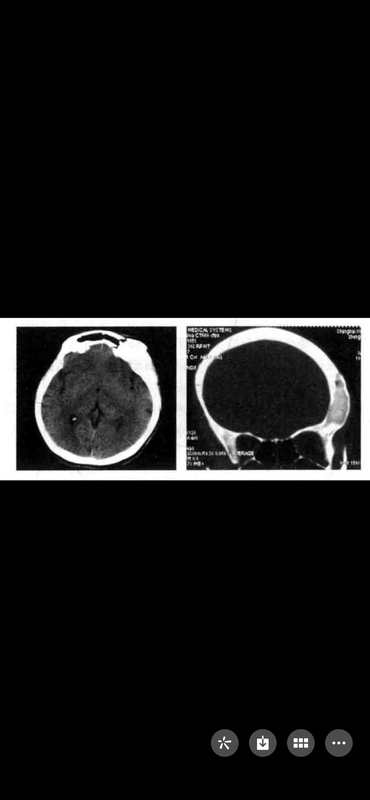

顱骨纖維結(jié)構(gòu)不良癥

顱骨纖維結(jié)構(gòu)不良癥(fibrousdysphasia)亦稱顱骨纖維結(jié)構(gòu)異常增生癥,病因不明,多數(shù)認(rèn)為是一種生理學(xué)上的障礙,沒(méi)有遺傳的證據(jù)。發(fā)病機(jī)制是成骨細(xì)胞的分化缺陷,使顱骨發(fā)育障礙,纖維組織替代骨質(zhì),導(dǎo)致顱骨變形、增厚,并非腫瘤樣增生。病灶好發(fā)于顱底、額骨、蝶骨,表現(xiàn)為頭部骨質(zhì)畸形、突眼、視力下降、頭痛及其他顱神經(jīng)麻痹。X線表現(xiàn):局部骨質(zhì)增厚、密度增高、不規(guī)則骨化、骨膨脹、囊性骨質(zhì)破壞、骨結(jié)構(gòu)模糊以及骨小梁消失呈“磨砂玻璃樣”改變。CT:骨質(zhì)局部增厚、骨密度高低混雜或增高、骨皮質(zhì)消失、骨板障增厚;增強(qiáng)后可見(jiàn)病灶明顯強(qiáng)化、密度不均。MRI:病灶信號(hào)混雜不均,多樣性。處理:一般情況下認(rèn)為是自限性疾病,25歲以后病灶繼續(xù)發(fā)展的可能性非常罕見(jiàn)。沒(méi)有明顯的顱神經(jīng)功能障礙,不建議手術(shù)治療。病變對(duì)化療、放療不敏感。顱蓋病灶可以通過(guò)刮除術(shù)和顱骨成形術(shù)治療。有明顯的眼球突出、視力下降,可行眶頂、視神經(jīng)管充分減壓,根據(jù)術(shù)前情況,選擇手術(shù)必須慎重。